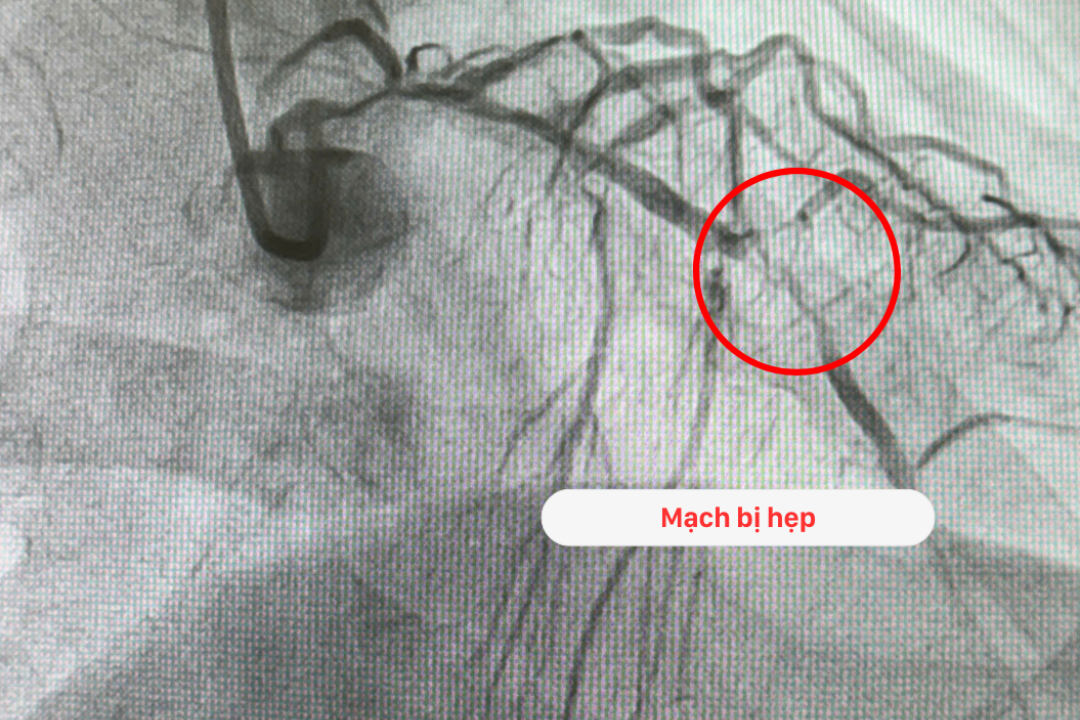

Kết quả chụp mạch vành số hóa xóa nền DSA của bệnh nhân cho thấy: Hẹp nặng >95% từ đoạn đầu của thân chung động mạch vành trái; Động mạch liên thất trước tổn thương lan toả, vôi hóa nặng, và tắc cấp gần như hoàn toàn từ cuối đoạn 1; Động mạch mũ hẹp nặng (90%) trong khi đó động mạch vành phải tổn thương tắc mạn tính hoàn toàn.

Theo Ths.Bs Nguyễn Văn Hải - Trưởng khoa Tim mạch - Tim mạch can thiệp BVĐK Hồng Ngọc: “Mạch chính nuôi tim của bệnh nhân T bị tắc rất nặng. Đây là mạch làm nhiệm vụ cung cấp máu chính cho tim. Với những trường hợp nhồi máu cơ tim, sốc tim, thể trạng sức khỏe yếu như bệnh nhân T thì tiên lượng rất nặng, cơ hội sống gần như bằng không vì khả năng ngừng tim có thể xảy ra bất cứ lúc nào”.

Hình ảnh hẹp mạch vành phức tạp của bệnh nhân T